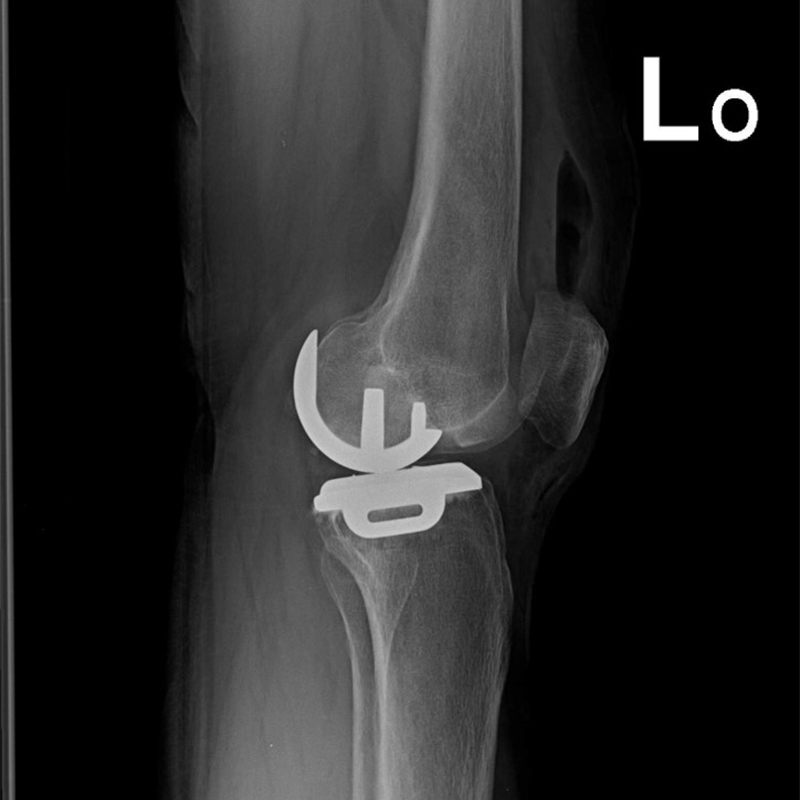

傳統部分膝置換 首頁 案例分享 膝關節手術 傳統部分膝置換 殷女士 65歲 術前 術後 張女士 71歲 術前 術後 蔡女士 74歲 術前 術後 張女士71歲 術前 術後 翁女士70歲 術前 術後 劉女士 80歲 術前 術後